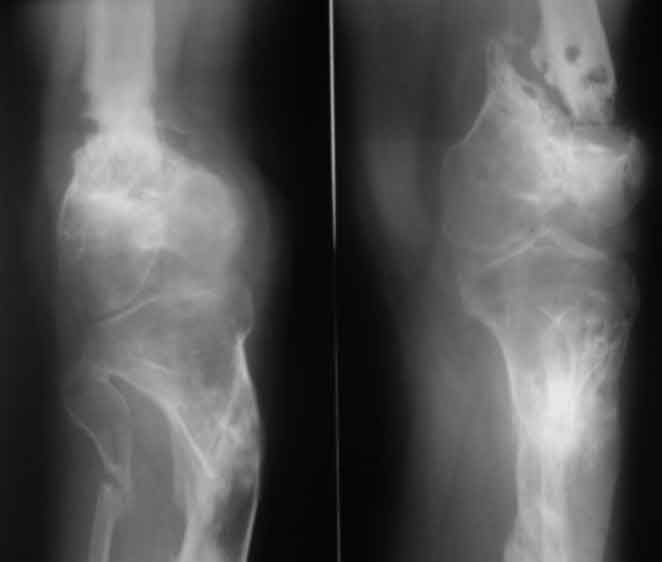

Псевдоартроз дистального отдела бедра. Distal femur nonunion у пациента 26 лет

Открытый перелом н/3 бедра и в/3 голени в 2006 году. выполнен малоинвазивный накостный остеосинтез после заживления ран (снимки утеряны), через 3 мес после остеосинтеза - глубокое нагноение, консультировался и лечился с 2006 года в одном из лучших НИИ. многократные остеотомии, компрессии, дистракции. В августе 2010 - снят аппарат в поликлинике в центре, рекомендации - ходить в ортезе, показаться через 2 мес, консультирован в другом НИИ - рекомендовано дообследование (приличный список, каждый раз добавлено нечто новое).

В итоге попал к нам, движения в к/с отсутствуют, подвижность только на уровне ложняка, передненаружная поверхность области к/с представляет собой многочисленные рубцы от доступов, закрытых свищевых ходов. Свищей нет на протяжении 3 лет, кровь не воспалительная, СРБ - отс.

Подскажите тактику. Размышляем гвоздь антеградно до метафиза б/б кости, пластина с костной пластикой по внутренней поверхности, кожно-мышечные лоскуты по наружной (для улучшения кровоснабжения) с какой-либо фиксацией? другие варинты (ЧКО в чистом виде пока не рассматриваем , т.к. делали до этого в более компетентном по этим вопросам учреждении)